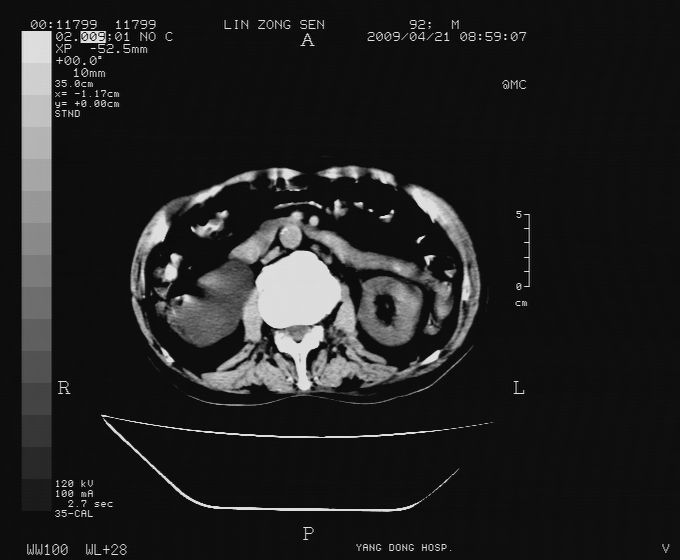

以下是引用卜一在2009-4-22 4:08:00的发言:[br]右肾积水伴输尿管上段积水!左侧肾多发囊肿!左侧腹壁软组织增厚,层次模糊,内密度较高—不排除血管瘤伴出血!